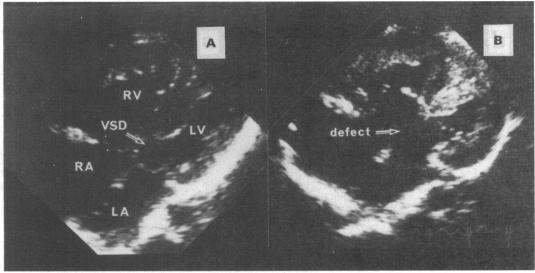

135 patients with typical AVSD and with nine patients with atypical AVSD, characterised by a well formed atrial septum, a milder downward displacement of the atrioventricular valves, and a shorter length of the ostium primum defect.

All nine patients with atypical AVSD had an unusual mean frontal QRS axis compared with six of the 135 patients (4%) with typical AVSD (p < 0.01). All eight patients who underwent the vector analyses showed atypical movement of the QRS loop--that is, an initial left inferior movement in the frontal loop (eight patients) and counter-clockwise rotation in the sagittal loop (seven). The corresponding values for 119 patients with typical AVSD were 20 and 22 patients (p < 0.01). Seven patients with atypical AVSD (78%) and 55 (41%) with typical AVSD had Down's syndrome (p < 0.05). None of the twenty one patients with additional cardiac anomalies had atypical AVSD, an unusual QRS axis, or unusual movement in the QRS loop.

135例典型AVSD患者和9例非典型AVSD患者,其特征为房间隔形成良好、房室瓣向下移位较轻以及原发孔缺损长度较短。

与135例典型AVSD患者中的6例(4%)相比,所有9例非典型AVSD患者的平均额面QRS轴均异常(p<0.01)。所有8例行向量分析的患者均显示QRS环运动异常,即额面环初始向左下运动(8例),矢状环逆时针旋转(7例)。119例典型AVSD患者的相应数值分别为20例和22例(p<0.01)。7例非典型AVSD患者(78%)和55例典型AVSD患者(41%)患有唐氏综合征(p<0.05)。21例合并其他心脏异常的患者中,无一例患有非典型AVSD、异常QRS轴或QRS环运动异常。